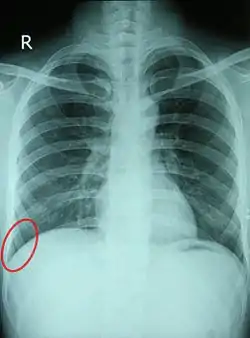

Chest X-ray of a 30-year-old healthy man, with the costodiaphragmatic recess label in red ellipse

Comparison between a normal costophrenic angle on the patient's right, and an obscured costophrenic angle (circled) on the patient's left, due to pneumonia with parapneumonic effusion.

In anatomy, the costophrenic angles are the places where the diaphragm (-phrenic) meets the ribs (costo-).

Each costophrenic angle can normally be seen as on chest x-ray as a sharply-pointed, downward indentation (dark) between each hemi-diaphragm (white) and the adjacent chest wall (white). A small portion of each lung normally reaches into the costophrenic angle. The normal angle usually measures thirty degrees.

With pleural effusion, fluid often builds up in the costophrenic angle (due to gravity). This can push the lung upwards, resulting in "blunting" of the costophrenic angle. The posterior angle is the deepest. Obtuse angulation is sign of disease.

Chest x-ray is the first test done to confirm the presence of pleural fluid. The lateral upright chest x-ray should be examined when a pleural effusion is suspected. In an upright x-ray, 75 mL of fluid blunts the posterior costophrenic angle. Blunting of the lateral costophrenic angle usually requires about 175 mL but may take as much as 500 mL. Larger pleural effusions opacify portions of the hemithorax and may cause mediastinal shift; effusions > 4 L may cause complete opacification of the hemithorax and mediastinal shift to the contralateral side.